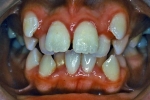

治療後2年経過時